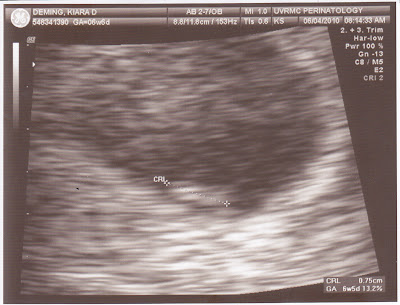

I had an early 7 week ultrasound. It was a HUGE relief to be able to see our little Sticky-Bun & an even bigger relief to hear the baby's heartbeat. We heard the heartbeat again at 10 weeks and then again this morning. We're extremely happy that this one is sticking so far and have our fingers crossed that we'll go all the way to full term.